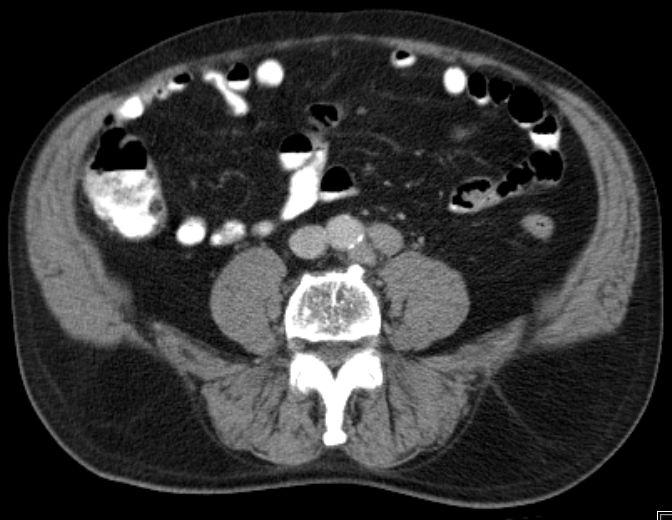

iliaca externa und inguinal |

59-jährige Frau mit einem Knoten in der linken Leiste.![]() |

![]() |

![]() | |